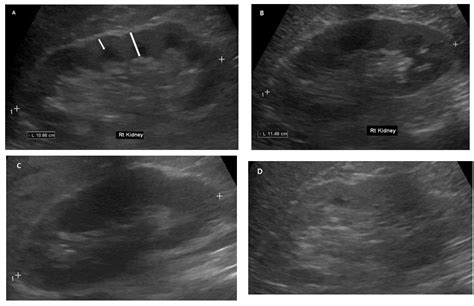

• Imaging tests, such as ultrasound or CT scan, to visualize the kidneys and urinary tract

• Imaging tests, such as ultrasound or CT scan, to visualize the kidneys

• aki vs ckd ultrasound